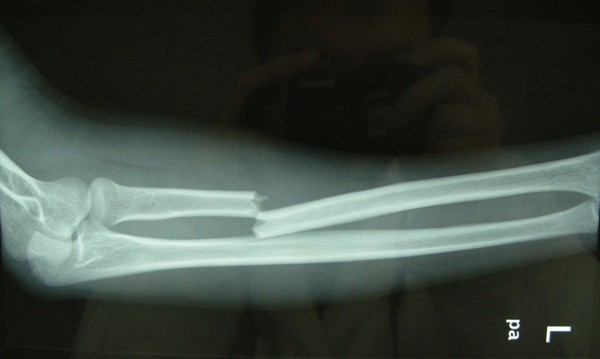

今日,三院骨科专家一一为病人解开疑惑,很多骨折病人需要进行切开复位内固定手术。但是,骨折通常伴有局部肿胀,这种开放性手术的时机,要根据骨折部位的肿胀程度来确定。有部分病人不理解手术和消肿之间的关系,很容易对医生产生误解。

如果病人骨折处肿得很厉害,一般要先消肿。否则,若强行进行内固定手术,容易并发感染。

不同的骨折部位,情况也是不一样的。例如:肌肉丰富的大腿部位,较轻的肿胀也可以做手术,这是因为该处肌肉比较丰富,做完手术之后软组织可以覆盖手术切口。然而,像小腿的胫骨、足部的跟骨等部位,软组织较少,属于皮包骨,倘若肿胀很严重时使用钢板进行内固定,手术以后将会出现软组织覆盖不了,皮肤也缝不上的状况。所以,这些情况必须先消肿再手术。

随着相关知识的普及,病人也渐渐能理解,肿胀严重却强行手术,将会导致皮肤感染、皮肤缺损、钢板外露和骨髓炎等危害。